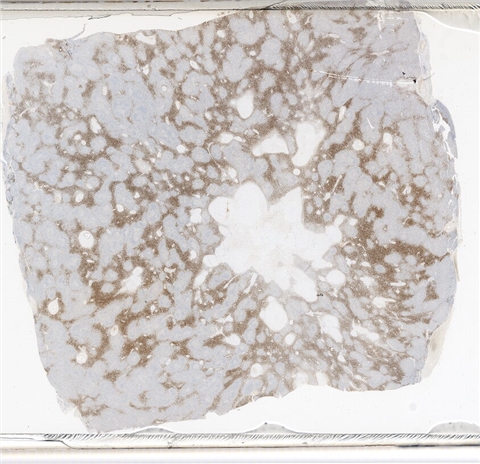

案例3 (6862)

性别:       年龄:65

患者详情: 患者3月余前在当地社区卫生服务中心体检发现血肌酐升高(109.8umo/L),无明显尿量减少,无颜面下肢浮肿无腰酸腰痛,无肉眼血尿,无关节疼痛,无皮疹红斑,开始未重枧及进一步诊治。10余天前患者到中山医院复查生化提示“肌酐200umol/L、尿素7.3mmol/L、尿酸637umol/L、白蛋白34g/L、球蛋白66g/L、蛋白电泳β15.0%、蛋白电泳Y42.6%”,同时其它检查提示“血lgG4 54.20g/L”。 CT:纵隔及双侧腋下多发肿大淋巴结,肺动脉干稍増粗,主动脉硬化,扫及双肾饱满,后腹膜发淋巴结。 PET-T:全身多区域淋巴结肿大、双侧泪腺、双侧颌下腺及胰腺体尾部饱满、双肾实质肿胀,左侧头皮局部增厚,伴FDG代谢增高,鼻咽顶后壁及前列腺腺体FDG代谢增高,上述病灶首先考虑IgG4相关性疾病所致可能,建议暖股沟淋巴结活检病理明确除外淋巴瘤。

大体所见: 结节一枚3*3*2cmA-C。

医院: 上海交通大学医学院附属仁济医院